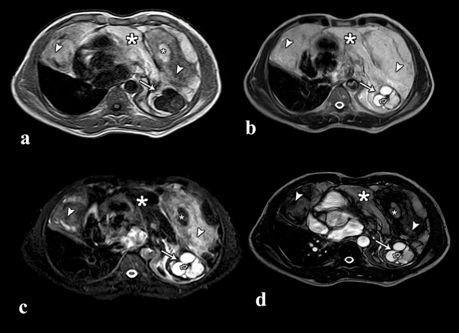

The radiograph of chest showed large ill defined radiodense opacity, centered at mediastinum and extending into hemithorax on both sides (Figure 1a). On lateral radiograph, there is obliteration of retrosternal clear space indicating the anterior mediastinal location of mass lesion (Figure 1b).

Figure 1: (a) Posteroanterior radiograph of chest showing large ill defined opacity involving mediastinum, extending into hemithorax on both sides, (b) Lateral radiograph of chest showing radiodense opacity filling the retrosternal space (arrow).